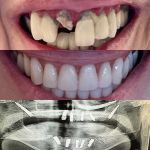

Dr. Eddie C. Chen, DMD & Associates Photos